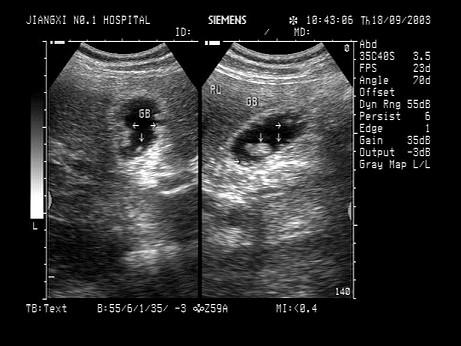

问题 超声见胆囊壁上大小约3mm的稍强回声光团,无声影,无移动,如图所示,考虑为?(?)

选项 A.胆囊结石 B.胆汁淤积 C.胆囊息肉 D.胆囊癌 E.以上都不是

答案 C